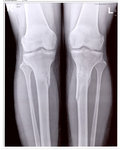

рентген в 90 дней.

Здравствуйте, Iskorka! По рентгену, сращение отличное, ждём на снятие аппаратов.